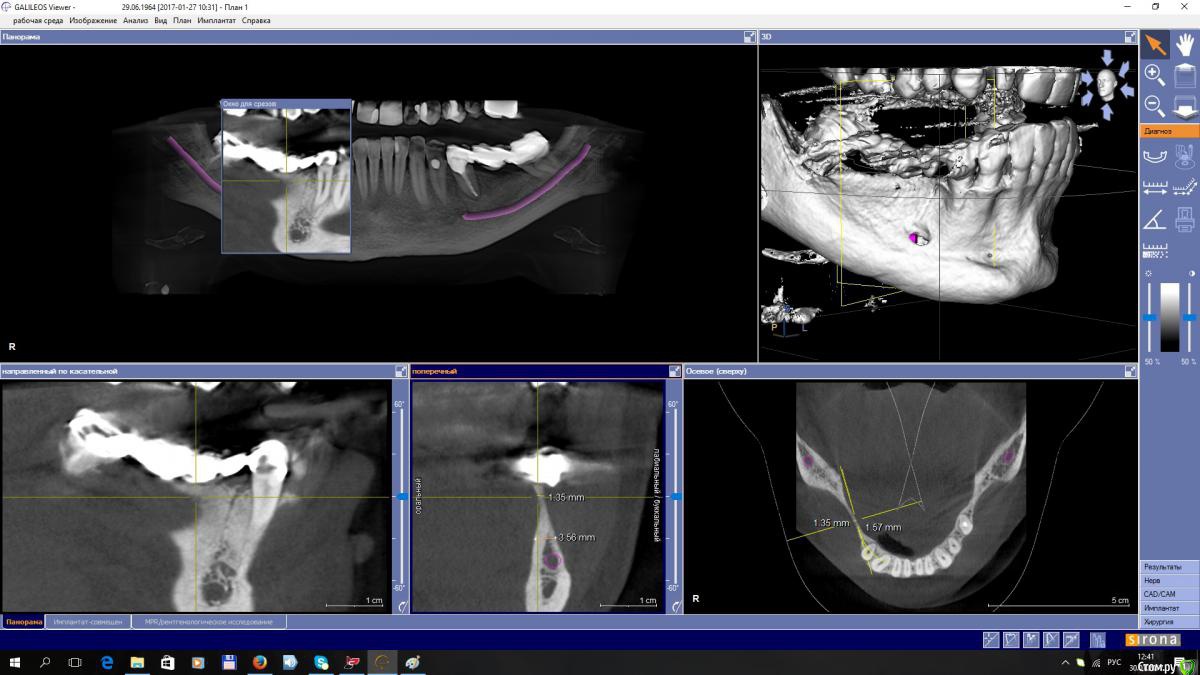

EEcho Опубликовано 27 января, 2017 Поделиться Опубликовано 27 января, 2017 (изменено) Уважаемые коллеги!Прошу совета!? Как увеличить объём, каким методом? Я в затруднении. За ранее большое спасибо! Изменено 27 января, 2017 пользователем EEcho Ссылка на комментарий

gum Опубликовано 27 января, 2017 Поделиться Опубликовано 27 января, 2017 А с язычной поверхности, углубление это дефект кости или сосуд там проходит? Ссылка на комментарий

EEcho Опубликовано 30 января, 2017 Автор Поделиться Опубликовано 30 января, 2017 покажите срезы дальше(дистальнее) может целесообразно провести аугментацию дистально, возможно там ситуация получше... и сделать медиальную консоль на 5ый зуб.Срезы в области 45, 46, 47,48, Ссылка на комментарий